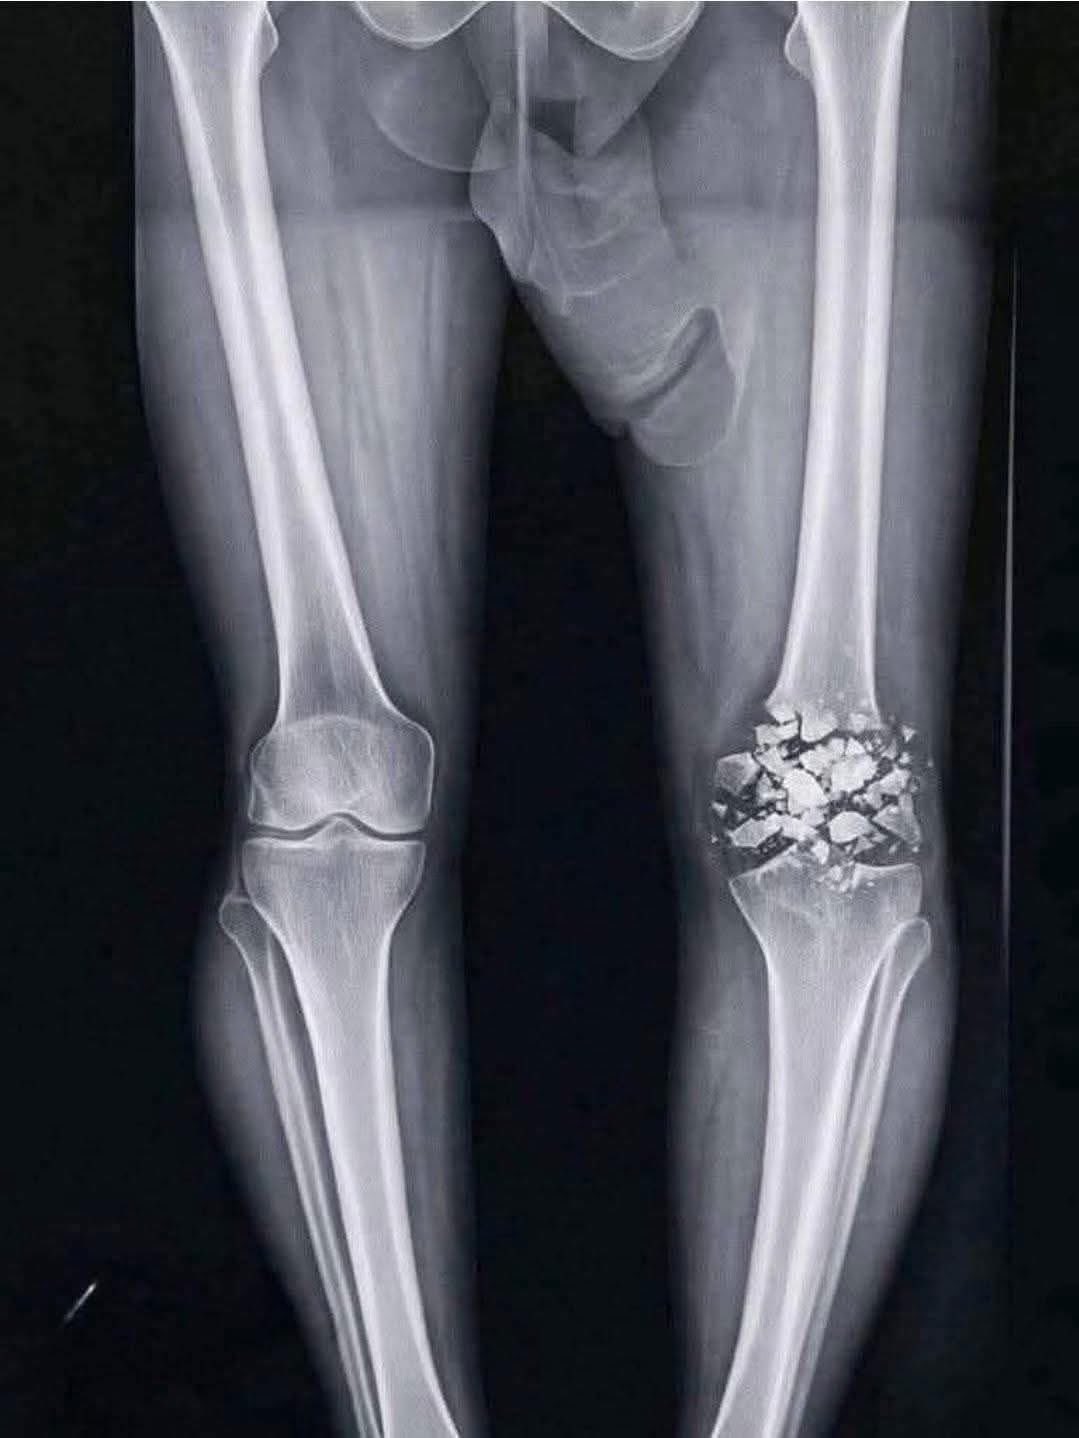

今こんな感じ

膝に矢を受けてしまってな

だが左膝が粉砕していたらどうかな…?

ここ最近話題になってるレントゲンチンコ

これ見るたびに膝と腰の位置どうなってんだってなる